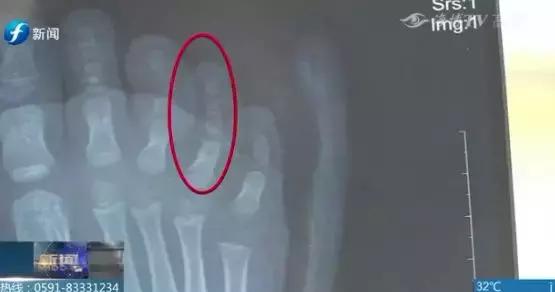

黄先生拿出了她女儿脚部受伤时拍的片子,第三根脚趾的第二个关节从中间断裂,而且脚趾严重变形。因为医院不接收,黄先生又赶忙把女儿转到了厦门大学附属第二医院。